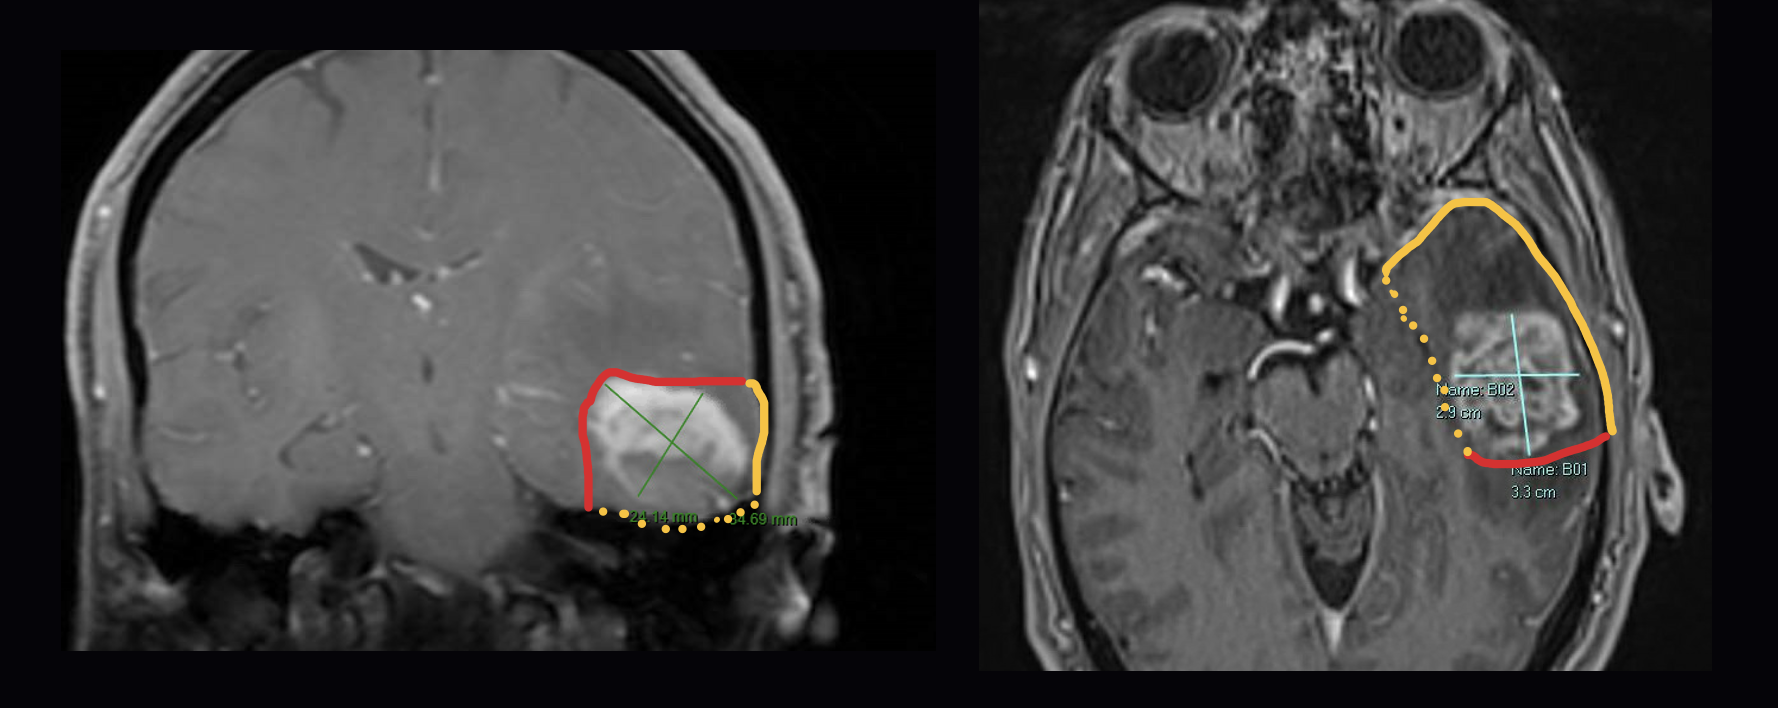

Tool for estimation of at-risk post operative tumor bed surface area

Assumes elipsoidal cavity with expected contraction.

The Brain Resection Cavity Estimation Tool is intended to assist with tumor bed calculations, based on relevant patient data, for patients undergoing tumor resection surgery with GammaTile.